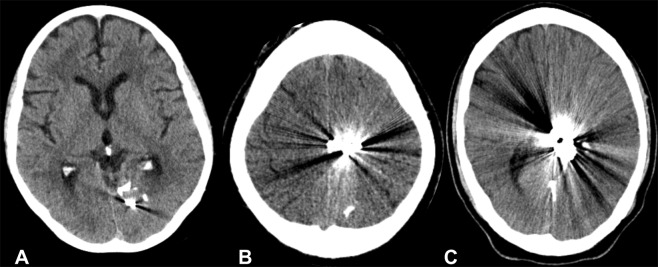

Figure 1.

Un-enhanced CT scans of the brain after embolization of Arteriovenous malformations (AVMs) with Onyx, in the left occipital lobe (A), in the left parietal region (B) and left parietotemporal region (C). Noticeable are the artifacts that reduce diagnostic image quality.